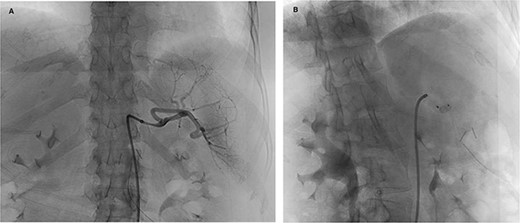

The patient was a 55-year-old female with relapsed large B cell lymphoma, severe thrombocytopenia with 17,000 platelets, and splenomegaly. Computed tomography (CT) (Fig. 1) and magnetic resonance (MR) (Fig. 2) images showed an enlarged spleen with multiple lesions, the largest measuring 3.5 cm, suspicious for lymphoma. Given the increased risk of intraoperative bleeding during splenectomy, a splenic artery embolization was performed the day before by using an Amplatzer plug (Fig. 3A and B), and platelets and fresh frozen plasma were prepared for the operation.

Preoperative splenic artery embolization (A: angiogram, B: post-plug deployment).